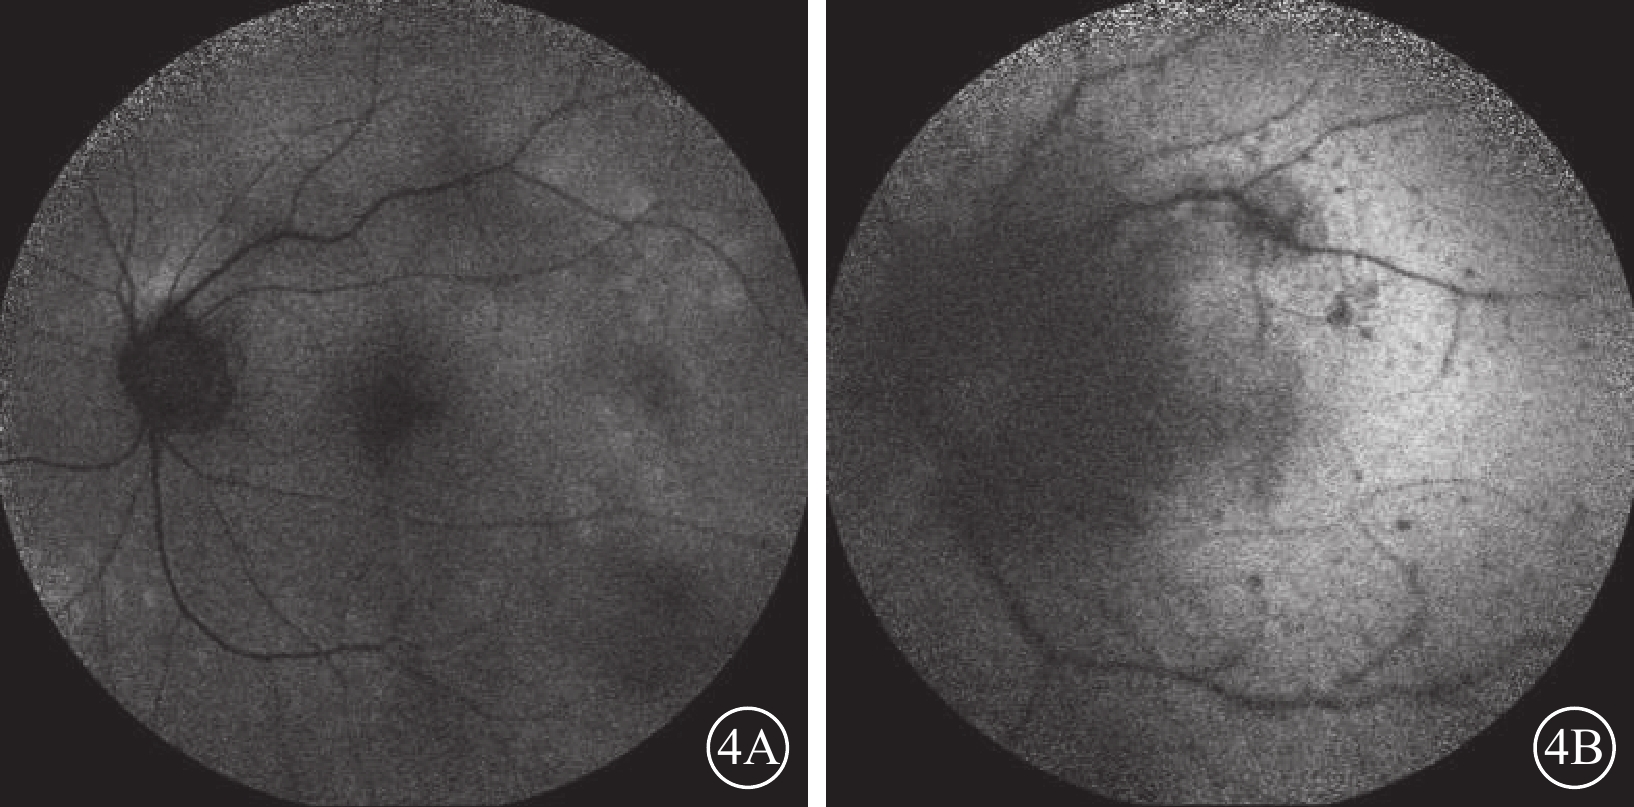

行AF檢查的8只眼中,“晚霞狀”眼底1只眼,表現為后極部散在稍強AF病灶,周圍伴有弱AF(圖4A);盤周黃白色病灶7只眼,表現為與彩色眼底像病灶對應處大小形態基本一致的弱AF病灶,其周邊及后極部存在散在點狀弱AF(圖4B)。